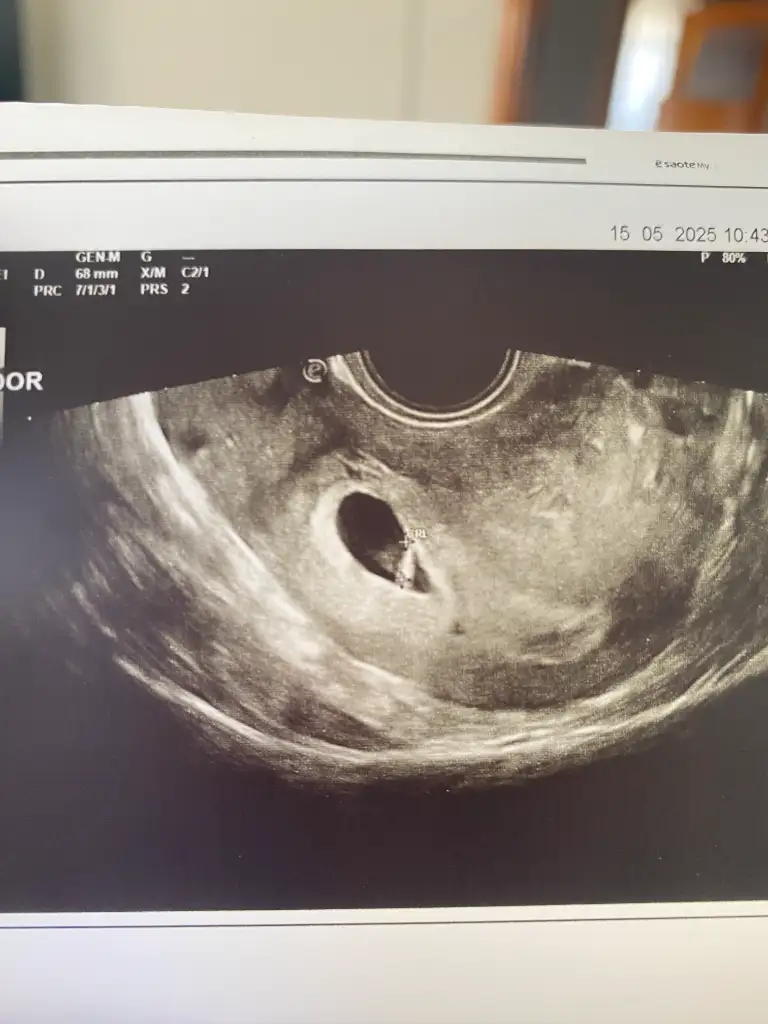

Benim de vajinal bakıldı ultrason yorum yapar mısınız sizce nedirKarindan mi vajinal mi peki

Ramziye göre kız ama daha çok erken tabi sağlıkla gelsinBenim de vajinal bakıldı ultrason yorum yapar mısınız sizce nedir

Benim de vajinal bakıldı ultrason yorum yapar mısınız sizce nedir

Yapay zeka da ısrarla erkek diyorRamziye göre kız ama daha çok erken tabi sağlıkla gelsin

Gerçi vajinal dediniz dimi çok özür dilerim kese sağda valla hamilelik bende dalgınlık yapıyorYapay zeka da ısrarla erkek diyorbeklemek çok zormuş ya

Yaaa banada bakarmisiniz rica etsem vajinal bakıldı bugünGerçi vajinal dediniz dimi çok özür dilerim kese sağda valla hamilelik bende dalgınlık yapıyorevet kese yerine göre erkek

Aynı canım kese sağda ramzi teorisine göre erkek sağlıkla gelsinYaaa banada bakarmisiniz rica etsem vajinal bakıldı bugün